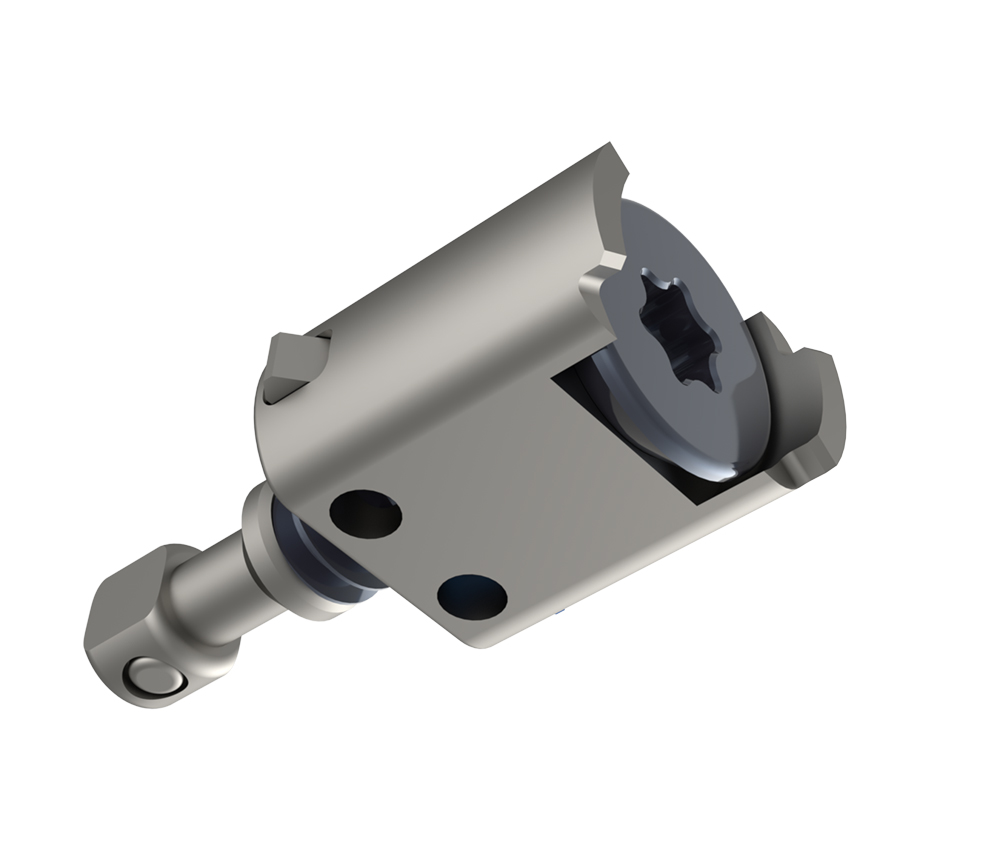

➢ N-GAGE™ Polyaxial Couplers

➢ N-GAGE™ Polyaxial Couplers

Designed for precision and simplicity, N-GAGE™ Couplers feature a NON-SCREW interface to connect effortlessly to X-PAC® LLIF Interbodies. Once in place, locking wings provide a secure, polyaxial connection to the interbody.

Designed for precision and simplicity, N-GAGE™ Couplers feature a NON-SCREW interface to connect effortlessly to X-PAC® LLIF Interbodies. Once in place, locking wings provide a secure, polyaxial connection to the interbody.

A polyaxial connection allows plates to conform to the lateral anatomy without compromising the interbody. Variable Depth Capture provides the ability to connect to interbodies inserted beyond the cortical rim.

Coronal Toggle: +/- 6 degrees

Rotational Toggle: +/- 7 degrees